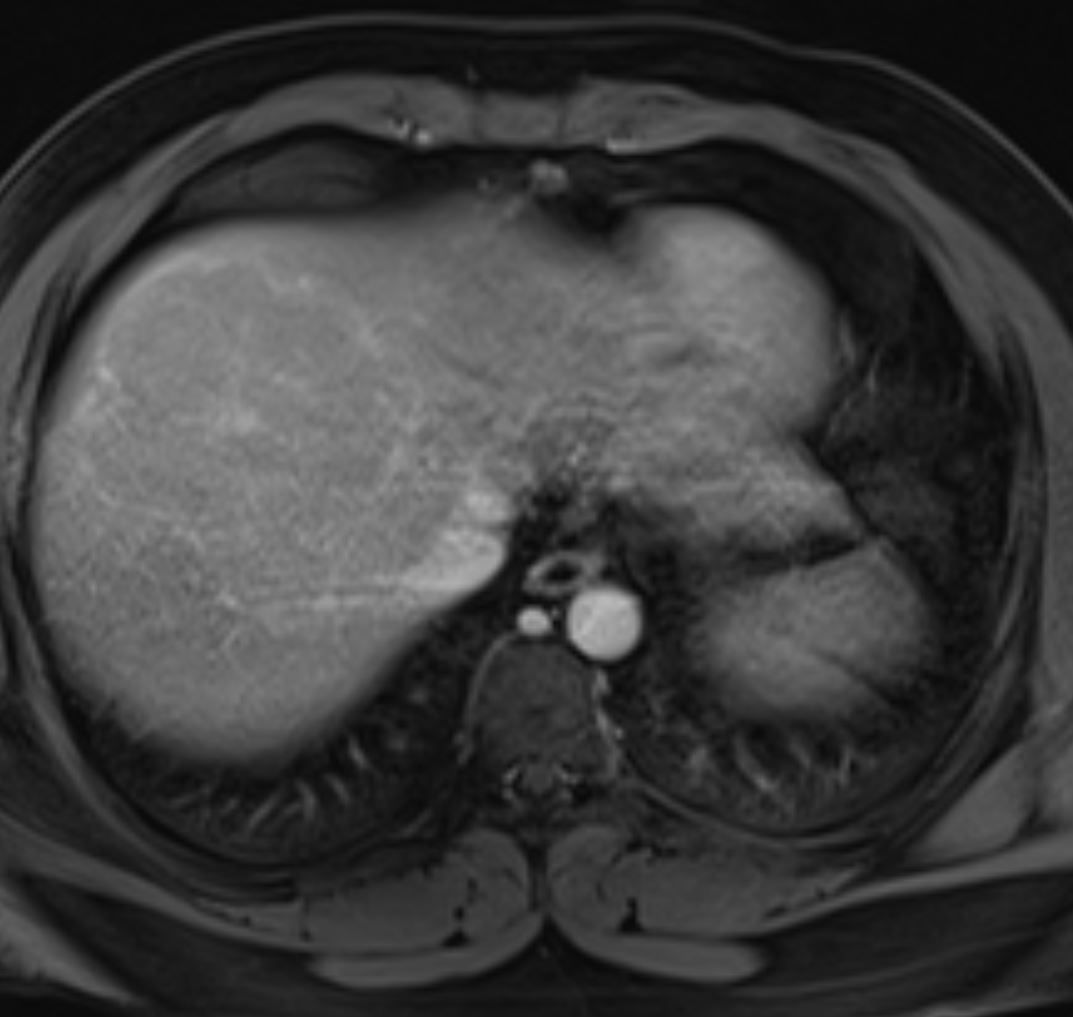

Young man presents with abnormal ultrasound and elevated liver function tests. What is the most likely diagnosis?

What is your diagnosis?